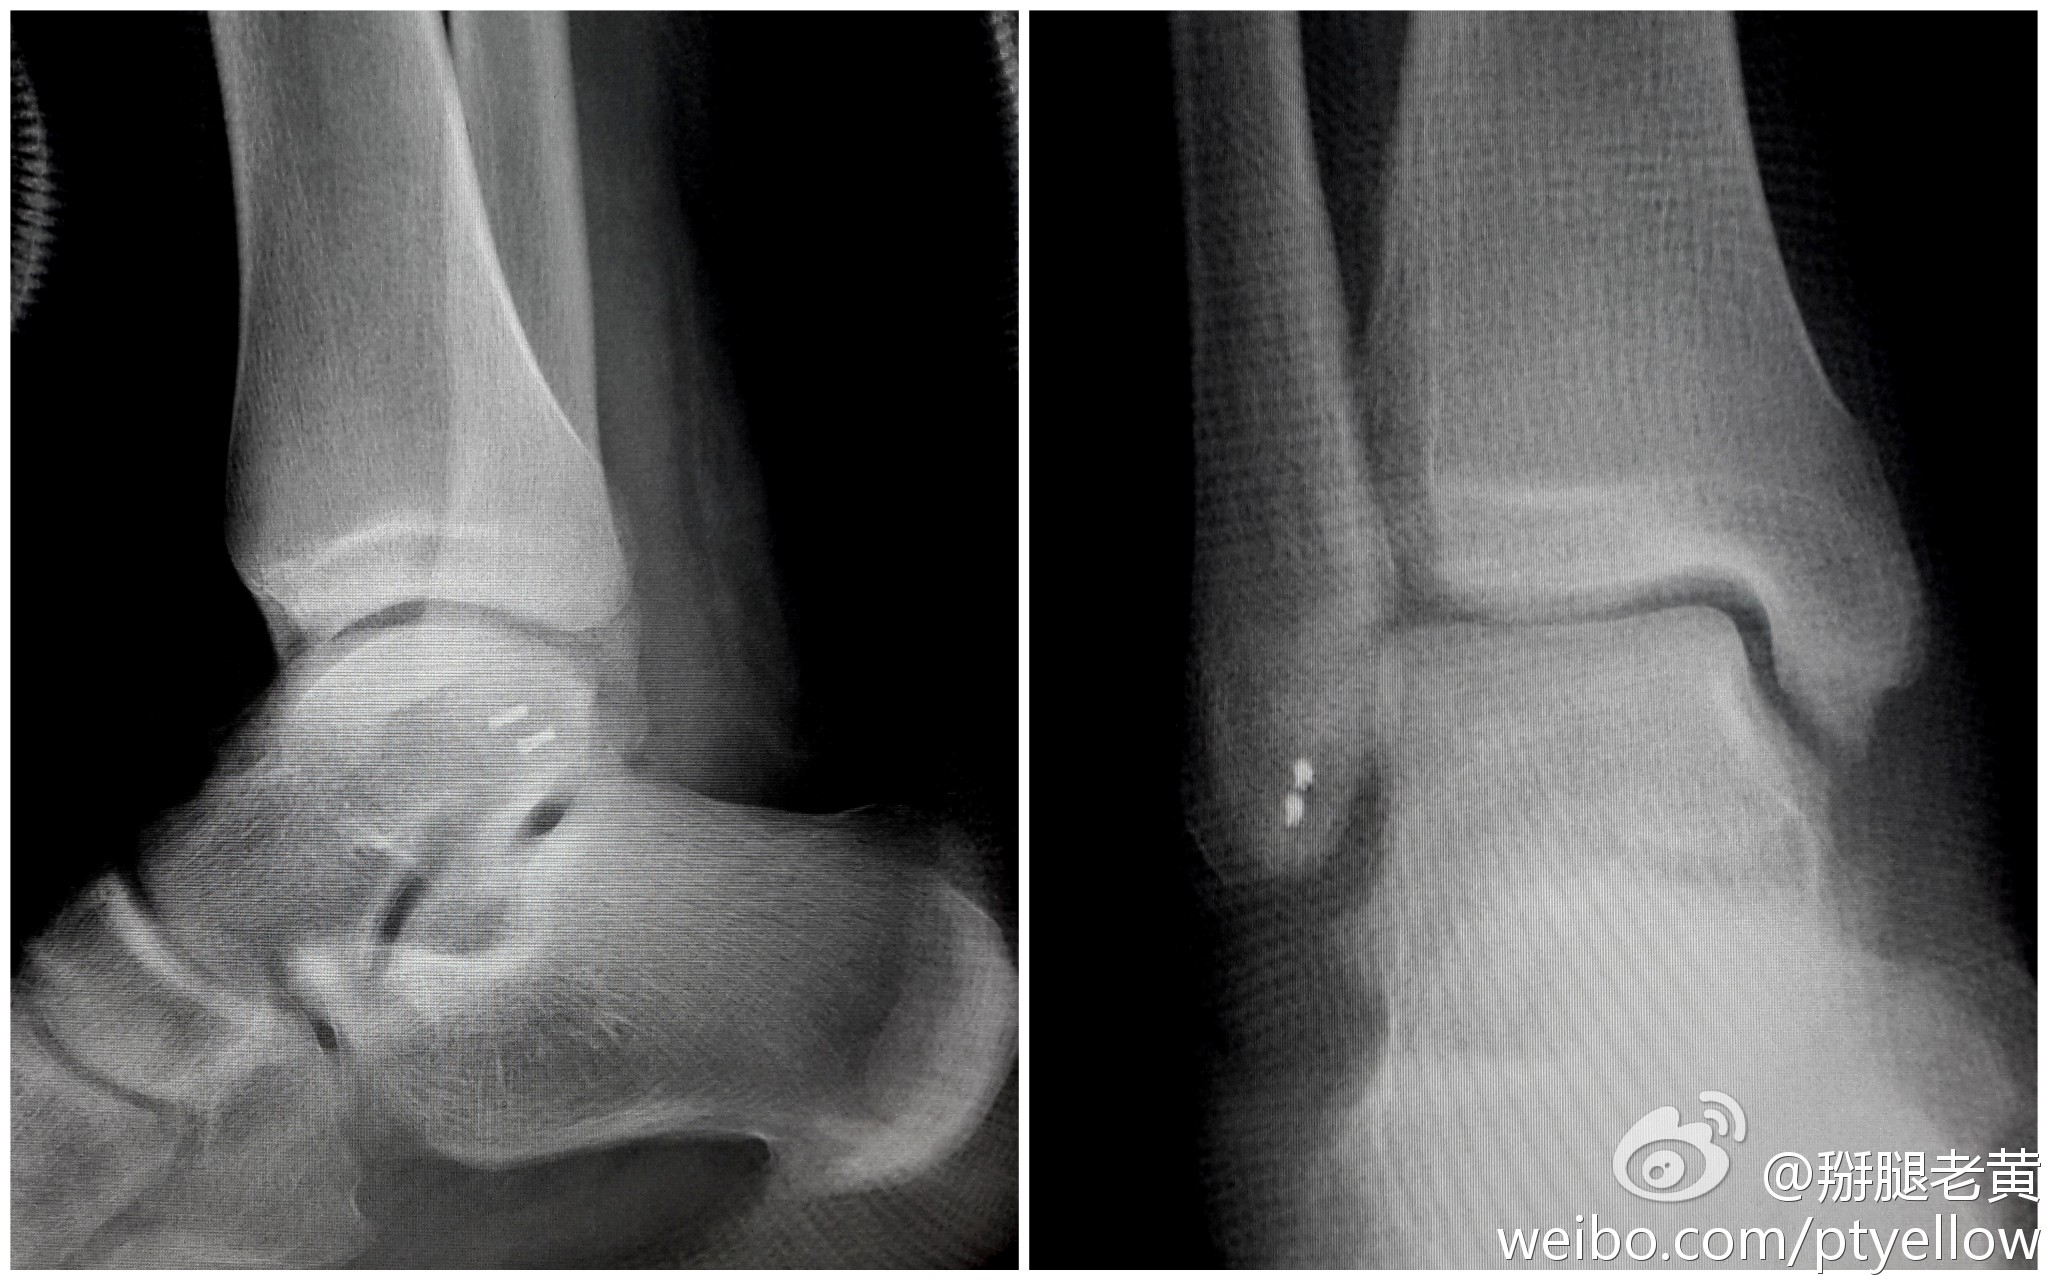

术前正位片子看三角韧带断了吗?需要修复吗?

图片尺寸640x734

病人踝扭伤住院,核磁报告有三角韧带损伤(没有片子),予以手术治疗,没

图片尺寸500x666